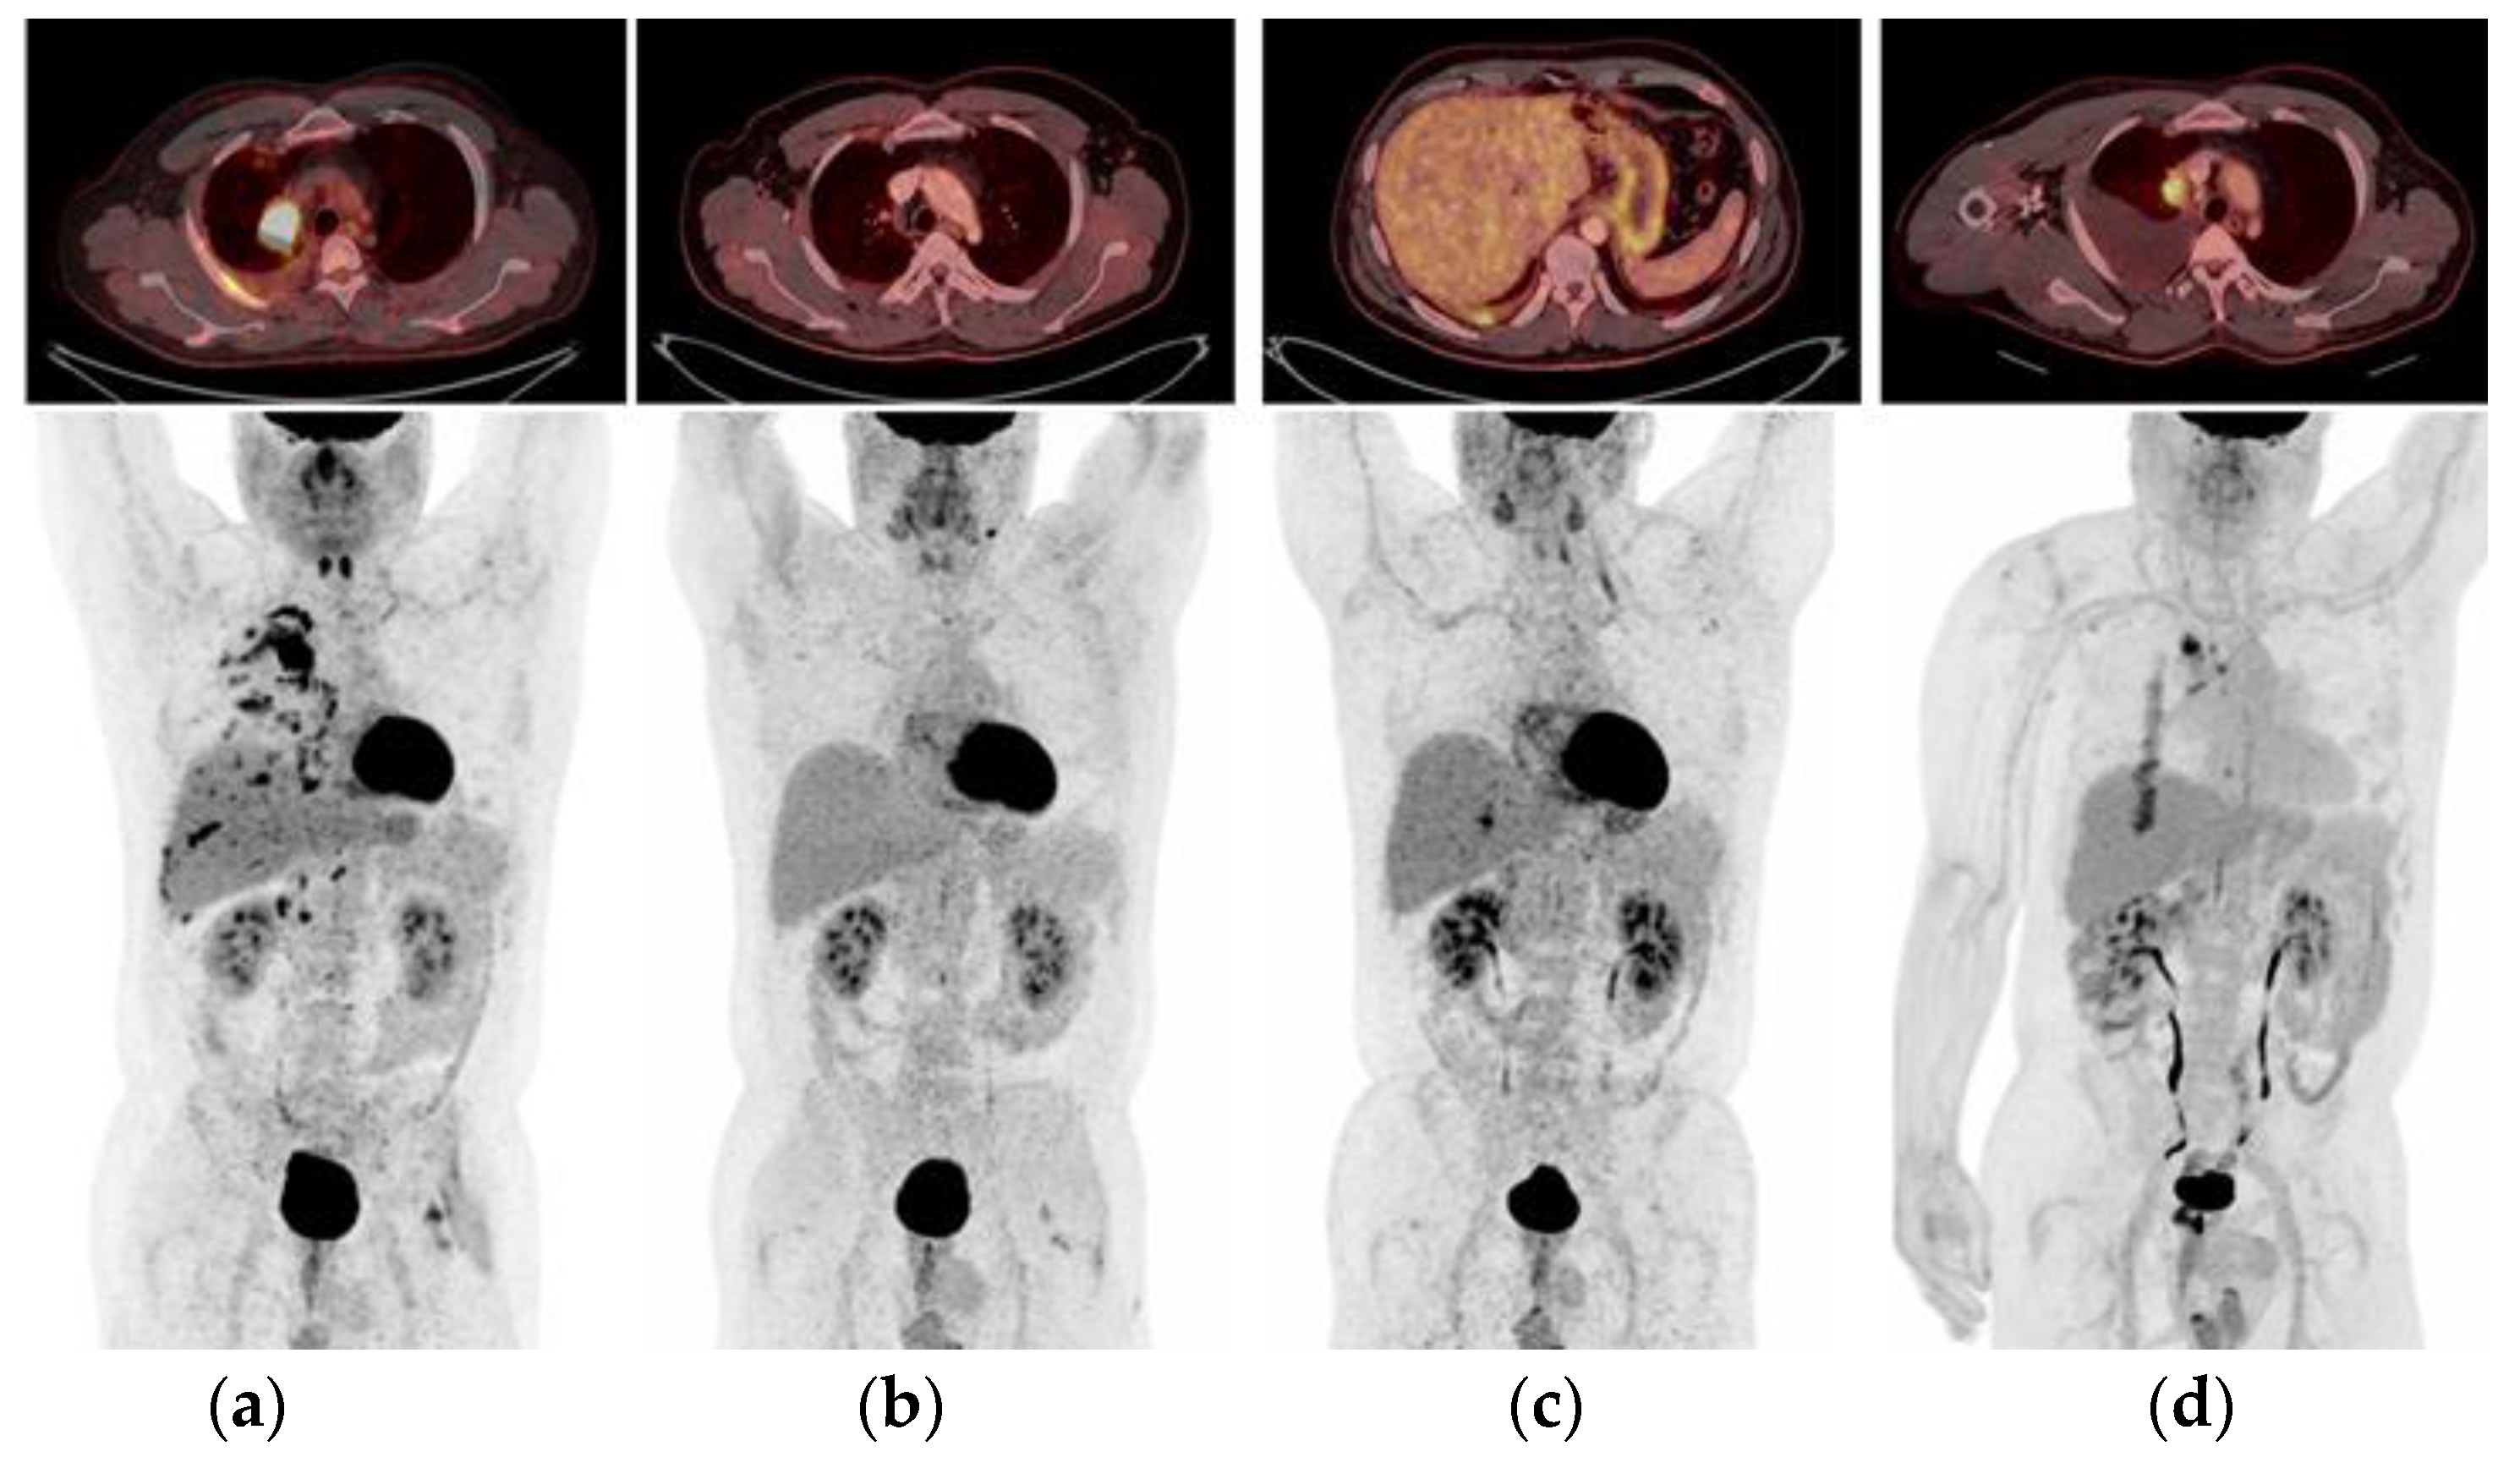

2.1. Case 1: Metastatic NSCLC with EGFR ex19del and Acquired MET Amplification: Short-Term Complete Response (CR) by Combining Crizotinib with Osimertinib

2.5. Case 5: Efficacy of Crizotinib-Osimertinib in EGFRm+ NSCLC Patient Acquiring High-Level MET Amplification after 26 Months of Treatment with Osimertinib